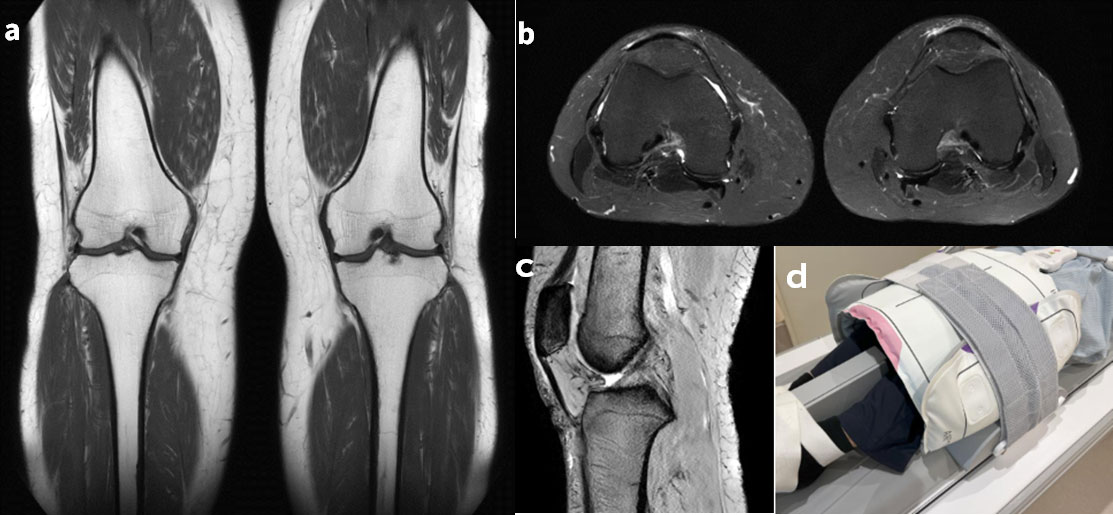

Fig.7-2は関節リウマチとACLの同時評価のために, 両膝MRIを施行した一例である. 従来であれば, クレードルの中央部に埋め込まれたTDI Posterior Array コイル(以下PAコイル)とTDI AAコイルによって撮像を試みるケースであるが, この手法だと, ACLを伸ばして描出するために膝を曲げると埋め込みPAコイルから距離が離れてしまい背面のSNRが低下してしまう. また, 埋め込みPAコイルがクレードル中央部にあることで, 患者の体はクレードルの上方に頭が飛び出した状態で寝ることになってしまう状況である.

AIR™ コイルはコイル同士の干渉が無いため, Fig.7-3cの様にAIR™ コイルを全周性に巻きながら, 一部が重なっても信号低下は生じない(Fig.7-2b). また, ブランケット型だからこそ, 膝にコイルを巻いた上で, 下にクッションを仕込むことができ, 膝背面のSNRを担保しつつ, ACLの伸展を確保できる. 寝台埋込コイルを使用しないため, 患者の寝る位置も気にする必要がなくなる. DLによるSNR向上効果により, 広い撮像範囲であっても, 通常の膝ルーチンに近いpixel sizeを保ちながら(Fig.7-2(a)(c)), 許容範囲内の撮像時間で検査を完結可能である.

Artist_Yokohamaminamikyousai10.jpgFig.7-2 AIR™ MP コイルCoil 2枚 (20ch + 21ch) を用いたRAとACL評価のための両膝MRI画像

(a) T1 Coronal (slice 3.5mm, pixel 0.54*0.54, 2:15)

(b) T2* Sagittal (slice 3.5mm, 47枚(両膝), pixel 0.64*0.64, 3:24)

(c) STIR Axial (slice 3mm, pixel 0.64*0.64, 2:37)

(d) コイルセッティング例 ( Air MP Coil (20ch + 21ch) )